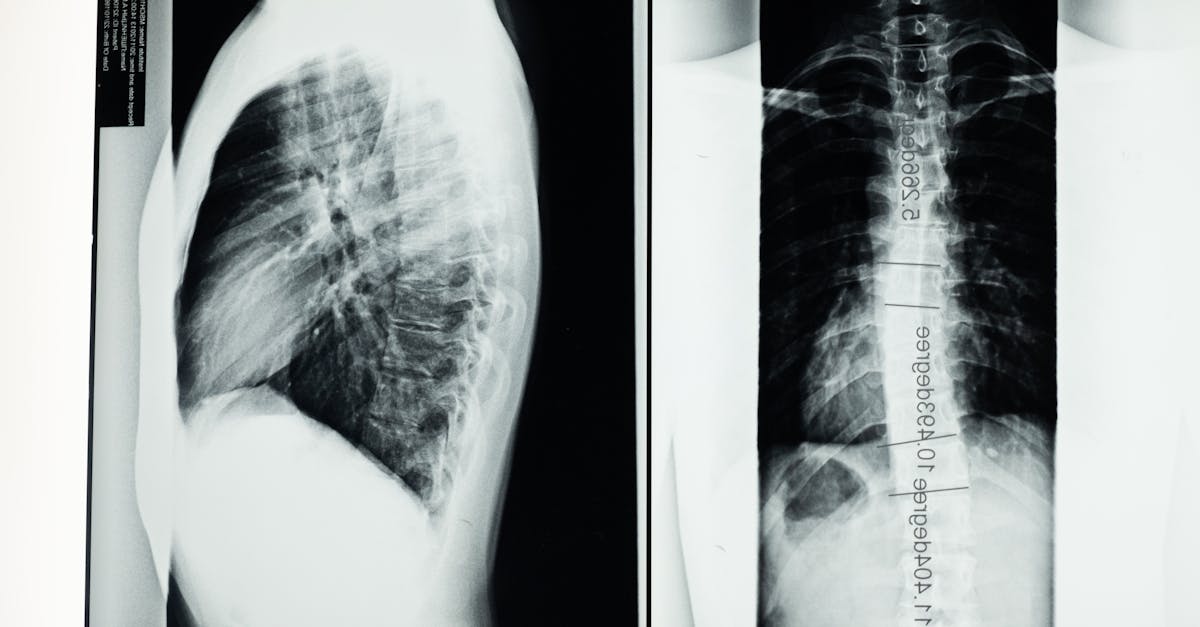

Likewise, when a patient presents symptoms of pulmonary embolism, a CT pulmonary angiography is often the preferred diagnostic tool to swiftly capture detailed images of blood vessels in the lungs. This rapid imaging capability is crucial in emergency situations where early detection is vital for prompt intervention and management. Therefore, in specific medical conditions characterized by the need for quick assessment and immediate results, a CT scan is typically favored over an MRI.

Moreover, CT scans are particularly useful for evaluating bone structures and detecting mineralized tissues. They provide clearer images of bones and dense tissues, making them more effective for diagnosing conditions like fractures, tumors, or bone infections. In orthopedic cases where precise visualization of bone injuries is necessary for treatment planning, CT scans are often the imaging modality of choice due to their ability to capture detailed images of skeletal structures with high resolution and clarity.

When considering detailed imaging needs, it is crucial to weigh the advantages of both CT scans and MRIs. CT scans are particularly adept at capturing images of bone and dense tissues like organs, making them an excellent choice for detecting fractures, tumors, or internal injuries following traumatic incidents. The speed of a CT scan also plays a significant role in emergency situations where quick assessment is vital for prompt treatment decisions.